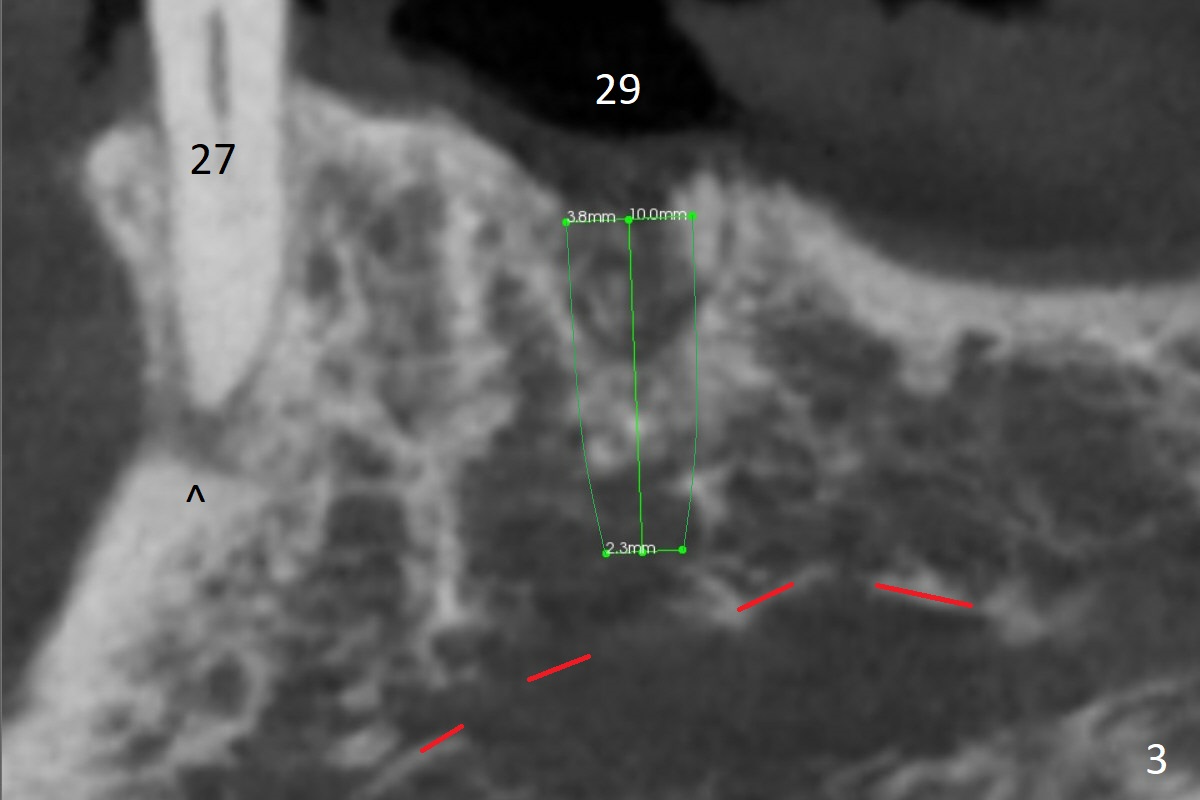

A 79-year-old woman with osteoporosis has a lower RPD, which becomes loose when #29 was extracted a few months earlier. The tooth #22 has mobility II (Fig.2 (increased pdl)), while the tooth #27 is short with periapical radiolucency (Fig.1,3 ^). The latter needs RCT and crown. For #29 implant placement, osteotomy should be underprep: 2 mm drill for 12 mm for 10 mm long implant (2 mm gingiva), 2.7 mm for 8 mm (Fig.3,4 (low bone density)).